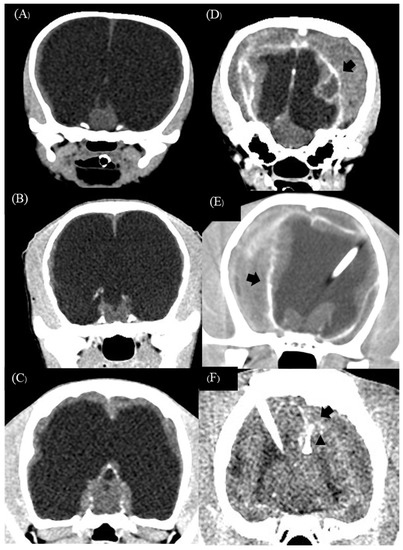

| 1 | Crossbreed | male | 2 | 2.4 | 3 | Mesencephalic aqueduct stenosis | 2.94 | 142.10 | 60 | 57.77 | Bilateral subdural hematoma and empyema |

| 2 | American Pitbull | male | 4 | 13.7 | 8 | Obstruction of interventricular foramen | 2.57 | 205.40 | 98.60 | 51.99 | Bilateral subdural hematoma and empyema |

| 3 | American Bully | male | 6 | 9.7 | 4 | Mesencephalic aqueduct stenosis | 3.68 | 139 | 7.57 | 94.55 | Bilateral subdural hematoma and empyema |

| 4 | Jack Russel Terrier | male | 6 | 1.6 | 12 | Mesencephalic aqueduct stenosis | 2.20 | 132 | 57.70 | 56.28 | Bilateral subdural hematoma |

| 1 | Disoriented Aggressive Right circling Conjugated nystagmus Both eye cortical blindness | Consciousness Reduced right circling Reduced aggressiveness | Shunt infection (6 weeks) Seizure Consciousness Reduced right circling Reduced aggressiveness | Death (parvovirus infection) |

| 2 | Obtunded Right circling Dysmetria Left eye cortical blindness Periodic oral automatism | Consciousness Reduced right circling Reduced dysmetria | Shunt infection (4 weeks) Seizure Consciousness Moderated right circling Improved learning ability Periodic oral automatism signs disappeared | Consciousness Continuously improved learning Mild right circling Seizure free Left eye cortical blindness |

| 3 | Obtunded Right leaning | Seizure (tramadol effect) Consciousness | Shunt infection (6 weeks) Consciousness Improved learning ability | Consciousness Continuously improved learning Seizure free |

| 4 | Disoriented Right circling Dysmetria Both eye cortical blindness | Disoriented Seizure Acute overshunting (72 h) | Disoriented Right circling and dysmetria Both eye cortical blindness Second shunt revision | Death (status epilepsy) |